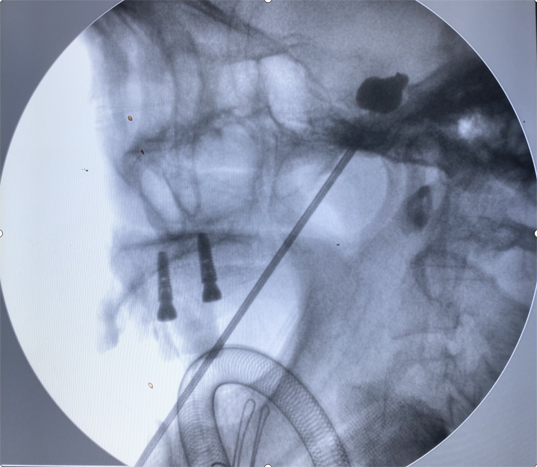

术前,团队通过磁共振和CT扫描获取患者的颅底空间三维数据,将这些数据输入机器人系统,并利用专业软件模拟患者的解剖结构,从各个角度观察并设计最佳手术路径。手术由神经外科邰军利主任医师和侯哲主治医师共同实施,术中机器人引导下的穿刺针精准定位,准确穿刺卵圆孔,球囊影像呈现“梨形”,效果满意。术后,李奶奶的疼痛感立刻缓解,并于第二天顺利出院。